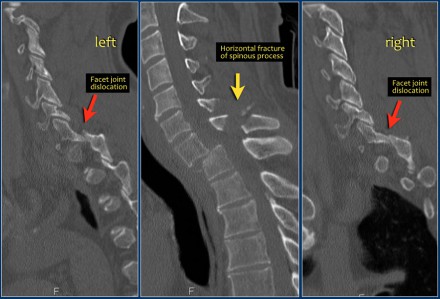

In this case of translation there is bilateral facet dislocation and also a horizontal fracture of the spinous process.

There is severe narrowing of the spinal canal.

The findings are:

- The main feature is posterior distraction with horizontal fractures of posterior elements (red arrow)

- Avulsion of a spinous process (yellow arrow)

- Widening of facet joint (green arrow)

- Burst-type fracture

In this case some would call this a burst fracture with PLC-injury i.e. 2+3 points.

However the distraction is the most important finding, i.e. distraction and PLC injury, i.e. 4+3 points.